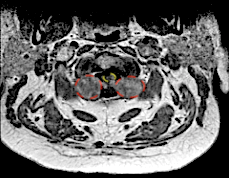

Imagen especular: en la derecha se ha marcado en rojo los schwannomas y en amarillo la médula. Se aprecian las raíces C2 engrosadas.